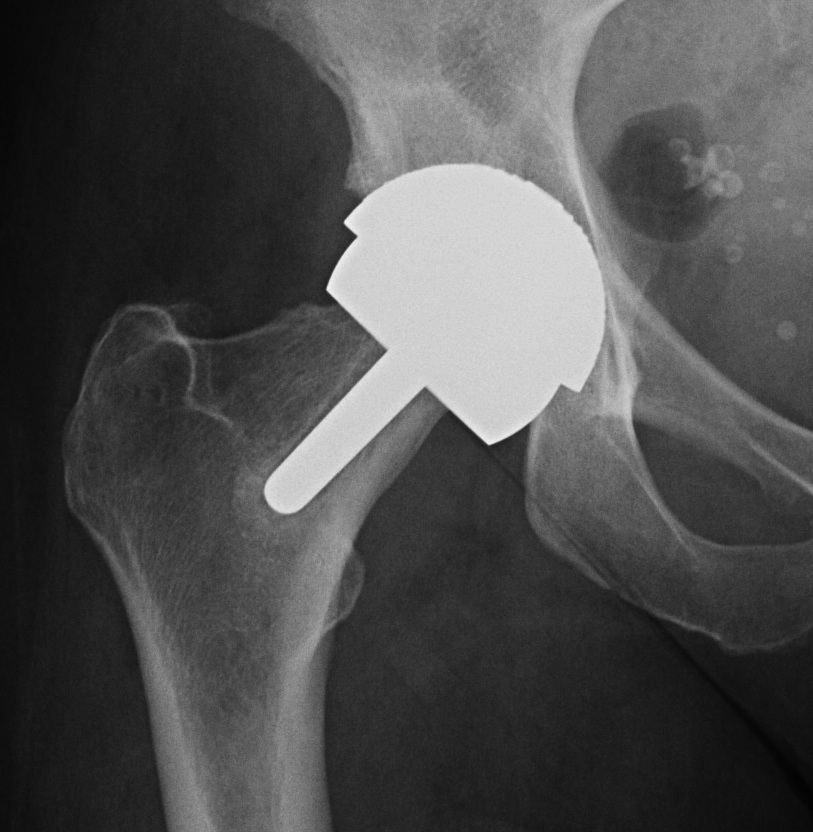

Concept

Femur - removal of femoral head cartilage and resurfacing with metal

Acetabulum - standard technique

Bearing surface - metal on metal

1. Femoral bone stock preservation

Male / OA / good bone stock / large femoral head size

Contra-indications (from: Birmingham hip resurfacing technical guide)

| < 50 mm templated head | |

Varus Femoral Component